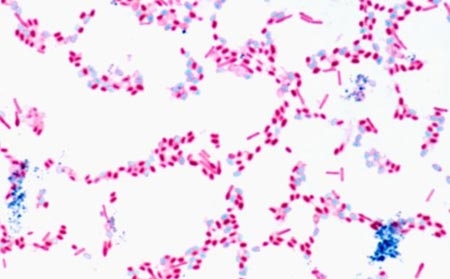

Vi khuẩn Clostridium botulinum. Ảnh: Corbis

Độc tố botulinum là một protein, chất độc thần kinh do vi khuẩn Clostridium botulinum sản sinh ra. Nó có thể vô cùng nguy hiểm và có khả năng gây tử vong cho người nếu được ăn vào bụng hoặc xuất hiện trong vết thương nhiễm trùng hoặc hệ thống dạ dày - ruột của trẻ em.